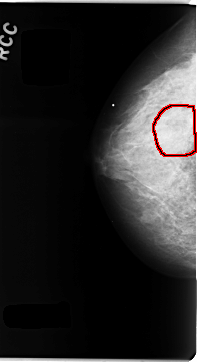

C_0107_1.RIGHT_CC

FILE: C_0107_1.RIGHT_CC.OVERLAY

TOTAL_ABNORMALITIES 1

ABNORMALITY 1

LESION_TYPE MASS SHAPE OVAL MARGINS ILL_DEFINED

ASSESSMENT 3

SUBTLETY 2

PATHOLOGY BENIGN

TOTAL_OUTLINES 1

BOUNDARY